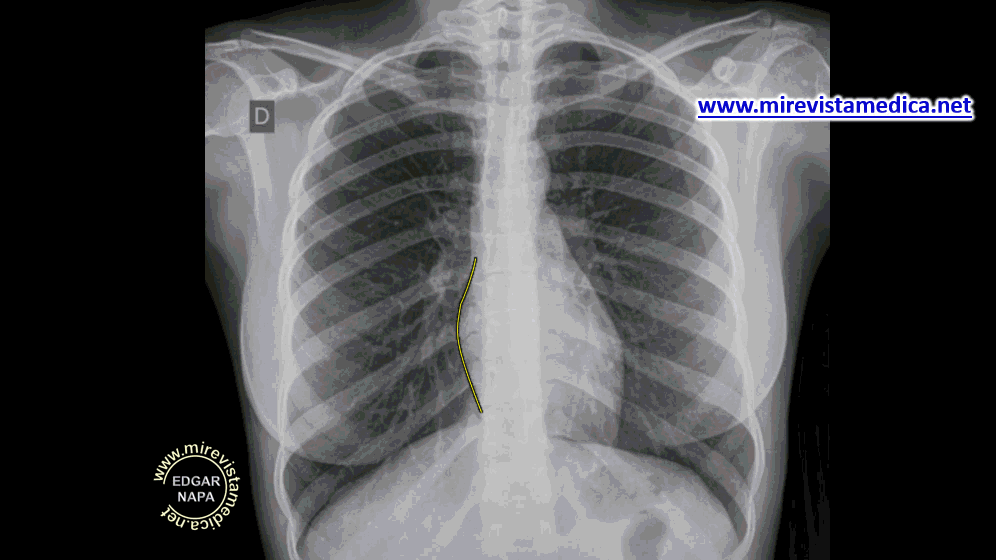

SILUETA ​​CARDIACA EN RADIOGRAFÍA